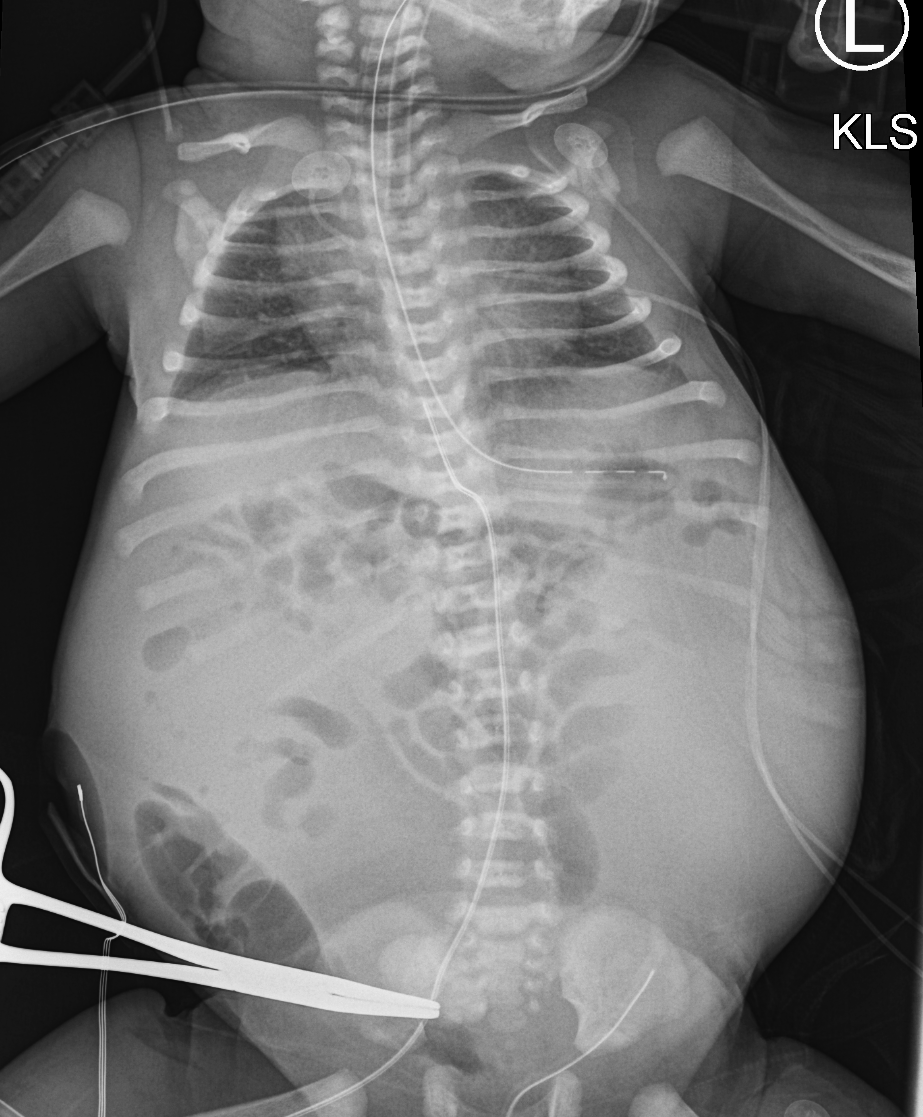

Info Images Findings Impression Reco/Acuity Case Images View Images / Launch Visage Case Notes History 2-month-old presents with decreased right arm movement, increased fussiness, and increased sleepiness for 2 days. Suspected non-accidental trauma. Exam Skeletal survey Prior Study none Dicom View Reference Material

Section 1 Submit Findings CB1550 Findings Skeletal Survey - Technique Check Skull AP/Lat Yes No Cervical and Thoracolumbar spine Yes No Chest X-Ray Yes No Ribs – Left/Right Oblique Yes No Abdominal X-Ray Yes No Pelvis with both hips Yes No Bilateral Humerus, Forearm, Hand Yes No Bilateral Femur, Tibia/fibula, feet Yes No Any additional lateral views of the extremities Yes No The exam is over or under penetrated. Yes No The exam may or may not be limited by overlying structures or soft tissues, body habitus, patient positioning, support devices, or motion. Yes No The area of concern is indicated by the patient, technologist, or care provider. Yes No The area of concern is included on the exam. Yes No Soft Tissues There is soft tissue swelling, indistinctness of fat/muscle planes, gas, or laceration in the area of clinical concern. Yes No There is an effusion, fat pad displacement, or fat fluid level. Yes No There is a radiodense or lucent foreign body. Yes No There are other densities, calcifications, post-surgical changes, or support devices in the soft tissues. Yes No Any support lines/tubes. Yes No Bone There is a break or interruption of the continuity of the cortical or cancellous bone. Yes No There is overriding of the trabeculae with apparent sclerosis. Yes No There is displacement of a fracture fragment. Yes No There is bowing of the bone in addition to the fracture at the apex of the bowed bone concerning for the greenstick. Yes No There is a spiral fracture of the leg concerning for toddler’s fracture. Yes No There is abnormal angulation or bulging of the cortical surface relative to the normal cortex which could be from a buckle or torus fracture. Yes No There is a displaced fragment which may be from avulsion by a tendon, ligament, or joint capsule or from a comminuted or other fracture. Yes No The stress trabeculae or other trabeculae of the cancellous bone are interrupted or otherwise abnormal. Yes No There is subperiosteal or endosteal reaction which could indicate a healing or subacute fracture or other abnormality. Yes No There is hard/soft callus formation. Yes No There is remodeling of the bone. Yes No There is a corner fracture or metaphyseal lesion that could be from nonaccidental trauma. Yes No There are multiple fractures of different ages. Yes No There are vertebral body/spinous process fractures. Yes No There are rib fractures. Location - posterior or lateral. Yes No There is scapular/sternal fracture. Yes No There are fractures of the digits. Yes No There are wormian bones. Yes No There are intrasutural bones. Yes No There is metaphyseal abnormality (lucencies, increased density, erosion) which may be from something other than injury such as stress, metabolic disease (e.g. rickets with loss or distortion of the zone of the provisional calcification), neoplasm (e.g. leukemia), heavy metals, inflammation, or infection. Yes No There are metaphyseal spurs. Yes No There are bony deformities involving multiple bones. Yes No The bones are gracile. Yes No There are non-healing fractures. Yes No There is/are focal or multifocal lytic/lucent, blastic/sclerotic or mixed density lesion(s) or other abnormality. Yes No Overall bone density is increased or decreased with or without thinning or thickening of the cortical or cancellous bone. Yes No Growth plates, ossification centers, apophyses The growth plate(s) is/are abnormal. Yes No There is widening of the physis from a fracture with or without displacement of the epiphysis (Salter-Harris I). Yes No There is a fracture through the physis which then extends into the metaphysis with or without angulation or displacement (S-H II). Yes No There is a fracture through the physis which then extends into the epiphysis and is intra-articular, with or without angulation or displacement (S-H III). Yes No There is a fracture through the metaphysis, physis, and epiphysis which extends into the joint space with or without angulation or displacement (S-H IV). Yes No There is narrowing of the physis from a compression fracture (S-H V). Yes No The apophysis, epicondyle, secondary ossification center, or accessory ossicle is displaced or otherwise abnormal. Yes No The ossification centers are underdeveloped. Yes No Joints and alignment There is an effusion, fat pad displacement, or fat fluid level. Yes No The epiphysis or subchondral bone is fractured, interrupted, flattened, compressed, impacted, displaced, or otherwise abnormal. Yes No There is an intra-articular loose body or chondrocalcinosis. Yes No The joint is widened, narrowed, dislocated, malaligned, or incongruent. Yes No There is pseudoarthrosis. Yes No Other findings There are developmental changes or other anatomic variants or other existing conditions that may or may not be contributing to symptoms which can or should be further evaluated non-emergently or are otherwise incidental. Yes No The remainder of the exam is abnormal for age. Yes No The lungs show focal airspace opacity. Yes No There is pneumothorax. Yes No There is organomegaly. Yes No There is intra-abdominal calcification. Yes No There is displacement of the bowel loops. Yes No There is free intraperitoneal air. Yes No The bowel loops are dilated/obstructed. Yes No There is paraspinal soft tissue abnormality. Yes No